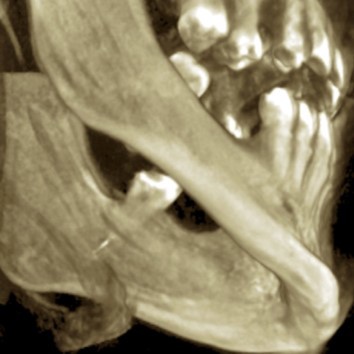

The patient’s symptoms and the close proximity of the broken instrument to the mandibular canal seen in panoramic radiography suggested that the broken endodontic instrument was in contact with the IAN. To confirm this diagnosis, CBCT examination was undertaken, and clearly showed the broken instrument in the periapical area of the mandibular left third molar and that the instrument was inside the mandibular canal. The result was the same as the panoramic examination, broken instrument was noted in the left mandibular canal Figure 3a, Figure 3b.

Figure 3a.CBCT surface examination broken endodontic instrument lodged in the mandibular canal.

Figure 3b.CBCT examination broken endodontic instrument lodged in the mandibular canal.